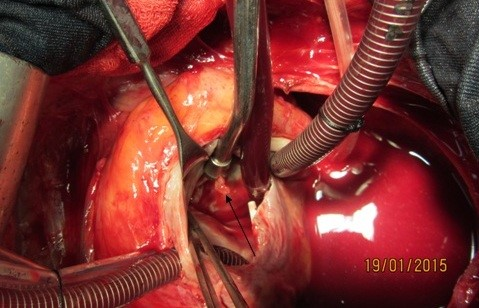

Figure 5: Vegetation in entrance of fistula tract to right atrium in tip of suction (black arrow)

A 37-year-old female patient was referred to our hospital following a full course of Brucella endocarditis in a general hospital for emergency surgery of Brucella endocarditis of aortic and mitral valve. The patient’s past medical history revealed living in endemic area of Brucella infection and a history of consumption of unpasteurized milk products. Her medical history was unremarkable except for sacroiliac arthritis. She had been admitted in a general hospital for assessing fever over the last month. After detecting a positive blood culture for Brucella without its bio-typing, she was treated by following triple combination of drugs consisting of oral rifampin 900 mg per day (qd), oral doxycycline 100 mg twice per day (bid) and gentamicin 80 mg intravenously three times per a day (tid) adjusted with blood levels of drugs and serum BUN and creatinine level. Upon admission, the patient was feverous, tachycardic, her blood pressure was low (80/20), and she had dyspnea. On neurologic examination, the patient was awake and oriented; her skin was cold and damp. The patient’s previous blood cultures at three different times showed a Brucella infection. White blood cell count: 12,000/mm–3 with 70% neutrophils, platelet count: 80,000/mm–3, hemoglobin: 9 g/dl, C-reactive protein: 60 mg/dl, erythrocyte sedimentation rate: 75 mm/h, blood urea nitrogen (BUN): 60 mg/dL, and creatine (Cr): 3.9 mg/dL. Urinalysis revealed no hematuria and 24-hour (diurnal) urinalysis (UA) revealed proteinuria. Serum agglutination tests were positive (titer>1:1,500), and enzyme-linked immunosorbent assay tests for anti-Brucella IgG and IgM antibodies were strongly positive (150 U/ml and 52 U/mL, respectively). A transthoracic echocardiogram (TTE) delineated destruction of mitral and aortic valves by multiple vegetation and multiple small and large aortic ring abscesses extended to surrounding tissue and perforated to right atrium, main pulmonary artery and formation a pocket over the left atrial roof (Figure 1 [Fig. 1], Figure 2 [Fig. 2]). The ejection fraction (EF) was 50% and pulmonary pressure was 60 mmHg. There was severe aortic, mitral and tricuspid valve regurgitation. The patient continued to use the previous anti-Brucella drugs orally while additional evaluations were performed. Due to the patient’s congestive heart failure (CHF) in addition to her multiple mobile aortic and mitral valve vegetation, it was decided that aortic and mitral valve replacement shall be performed immediately. The patient was scheduled for an emergency double valves procedure. However, the night before the surgery, she was intubated due to respiratory distress and was subsequently connected to mechanical ventilator. The patient suffered from severe pulmonary edema caused by CHF that required mechanical ventilation. After intubation, the patient became hypotensive and oliguric needing inotropic drugs use. The patient’s hemodynamic became stabilized and she was taken to the operating room. The intra-operative transesophageal echocardiogram (TEE) did not reveal any new findings. The patient was taken to operating room and a median sternotomy was performed and aortic and bi-cava cannulation was done. After opening the pericardium, it was found that the aortic root was severely attached to the surrounding tissue by inflammatory reaction caused by perforation of abscess in left coronary sinus to roof of left atrium as observed in TEE. The ascending aorta was cross-clamped, and after transverse transaction of the ascending aorta, cardioplegin was indirectly infused to coronaries ostium to induce cardiac arrest. After moderate hypothermic cardioplegic arrest, the umbilical tape was put around both the superior vena and inferior vena cavae and they were snared. The right atrium and left atrium were opened superior and inferior to the atrioventricular groove. Further, intra-operative inspection of right atrium showed small vegetations in crater of fistula entrance to right atrium in antero-medial region of tricuspid ring (Figure 3 [Fig. 3]). However, the tricuspid valve was not involved in infective endocarditis. Intra-aortic root inspection revealed a defect in non-aortic coronary sinus filled with necrotic materials and an abscess that perforated through the area above the tricuspid valve (Figure 4 [Fig. 4]). There was also a fistula between the left-coronary sinus, just near the left coronary ostium to the main pulmonary artery (Figure 5 [Fig. 5]). Further intra-operative perception of aortic root revealed a pocket filled by abscess through a defect in left coronary sinus just located over the roof of the left atrium (Figure 6 [Fig. 6]). In addition to the aforementioned fistulas, multiple vegetations were observed on both mitral and aortic valves that caused severe destruction of both valves causing grave regurgitation (Figure 7 [Fig. 7]). It apeared that mitral valve vegetations were caused by regurgitated aortic valve flow that impinged on aorto-mitral fibrous continuity and subsequently caused the penetration and destruction of the native mitral valve (Figure 8 [Fig. 8]). This infective tissue involved the valve. The abscess was completely debrided to restore and find underlying normal tissue. After debridement of the perforation’s site of the left coronary sinus and cleaning of the performed pocket over the left atrial roof, the aortic defect was repaired by fresh autologous pericardium patch that was used in the external side of the ascending aorta. The fistula tract to main pulmonary artery was closed from intra-pulmonary side of fistula by 4/0 proline sutures, as the closure of small fistula to right atrium. After closing of all three fistula and reconstructing the left sinus of valsalva and replacement of both valves, an oval-shaped fresh pericardial patch was utilized in a sino-tubular junction positioned just close to the superior vena cava, which helped in a tension-free approximation of aortotomy incision. Because the perforation of abscess along the conduction system caused bundle branch block and disturbances of other conduction branches, the atrial and ventricular epicardial pacing wires were used for sequential atro-ventricular pacing. The patient was admitted to the surgical intensive care unit for further control and treatment. Weaning from mechanical ventilation was complicated with tachypnea and grave respiratory distress. Extubation was delayed on the 9th post-operative day after performing a tracheostomy for the better cleaning of respiratory tract secretion and facilitation of extubation. Transient renal and hepatic failure also complicated the postoperative course of surgery. The serum blood nitrogen and creatinine raised to 90 and 5.5 subsequently and was managed accordingly by three times of peritoneal dialysis. Her hepatic and kidney dysfunction recovered relatively in 15th day of operation. A TEE in discharge time revealed a normal functioning of both bioprosthetic valves; however, a mild paravalvular leakage was observed in aortic position. Moreover, correction of all fistulas was successful and no residual flow signal in area of fistula repair was found. She was discharged home on the 25th day after admission.